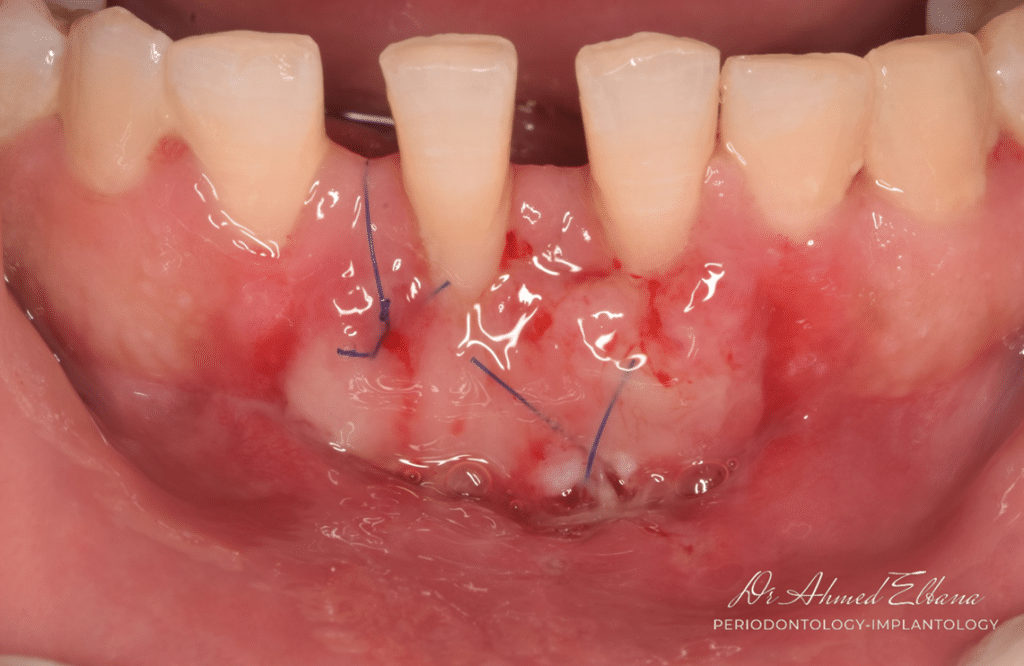

2- Recipient bed preparation.

using 15c scalpel blade horizontal incision at the level of MGJ extended to involve the defect. partial thickness flap preparation is performed to displace the muscle fibers in apical direction away from the denuded root surface.